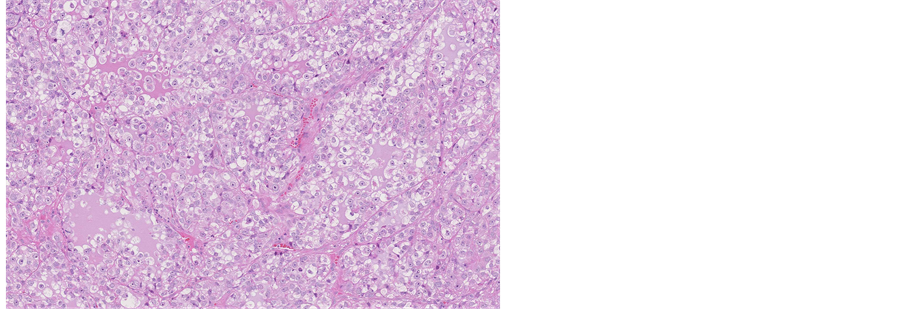

Histological evaluation of all specimens, removed from cervical cavity and obtained by biopsy revealed epithelial solid fields and cribriform areas of cells with enlarged nuclei and prominent nucleoli, atypical mitoses, partly eosinophilic and mostly significantly clear cytoplasm. Clear cell component was seen in 50% - 70% of the tumour (Figure 2).

Figure 2. Microscopic appearance of the endometrial tissue from curetting specimen-clear cell carcinoma, hematoxilin and eosin (H&E) staining, ×10.